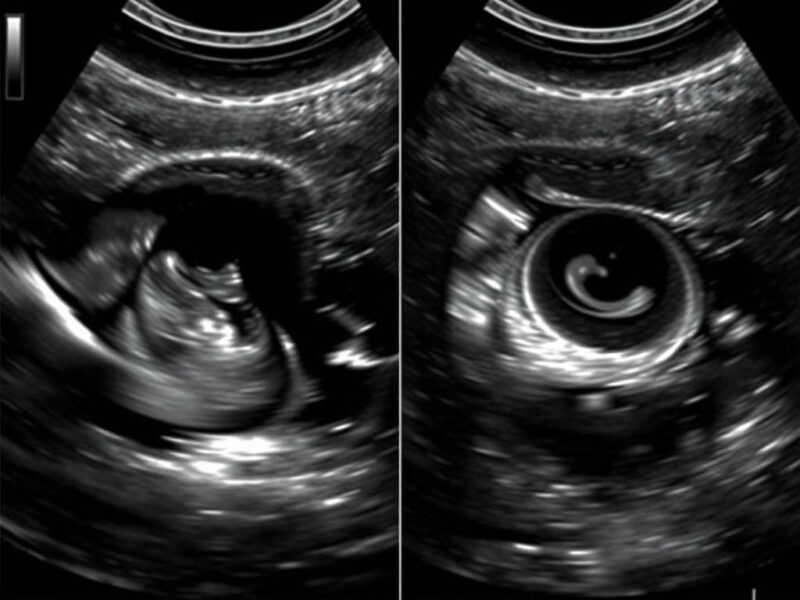

Distinguir un apéndice sano de uno inflamado implica observar varios elementos en conjunto, no un único signo aislado. El apéndice normal suele ser un tubo colapsable, difícil de seguir completamente y con diámetro exterior por debajo de 6 mm en la mayoría de las series. Un apéndice inflamado típicamente se presenta como un órgano tubular no compresible con un diámetro exterior aumentado (clásicamente >6 mm, aunque algunos autores usan >7 mm), pared engrosada, y alrededor un infiltrado de grasa hiperecoica que refleja inflamación periappendicular. El «Kokarde» o «target sign» aparece cuando el corte transversal muestra anillos concéntricos alternantes: una zona central menos ecogénica (a menudo el lumen con líquido o contenido) rodeada por una pared hipoecogénica y una capa externa más ecogénica. Ese patrón recuerda a una diana o a una «kokarde» (cocarde) en alemán; muchos ecografistas usan ambos términos —»target sign» y «Kokarde»— indistintamente.

- Imágenes en corte transversal con anillos concéntricos: «target sign» o «Kokarde».

| «Kokarde» / «target sign» | Anillos concéntricos hiperecogénicos e hipoecogénicos en corte transversal | Signo típico de apendicitis; aumenta la certeza diagnóstica |

Cuando hablo del «Kokarde» o «target sign» quiero que te imagines la imagen que se obtiene en el corte transversal de una estructura tubular cuyo lumen está rodeado por capas de pared con distinta ecogenicidad. Esa imagen en anillos recuerda a una “diana” o a una «kokarde» militar, y en ecografía abdominal es uno de los signos más llamativos de apendicitis. Sin embargo, como toda imagen, no es infalible: puede aparecer en otras patologías (por ejemplo, intestino inflamado en Crohn o un terminal ileitis) y a veces el apéndice inflamado no muestra de forma clara el patrón clásico. Por eso es importante valorar el signo en el contexto de los demás criterios.

Elementos que conforman el «target sign»

- Lumen central: puede contener fluido o material ecogénico y aparecer hipoecogénico o anecoico.

- Pared mucosa y submucosa: puede ser hipoecoica cuando hay edema.

- Capa muscular y serosa: puede aparecer más ecogénica, formando un anillo externo claro.

- Grasa periappendicular: aumenta la ecogenicidad alrededor y resalta el signo en el corte transversal.